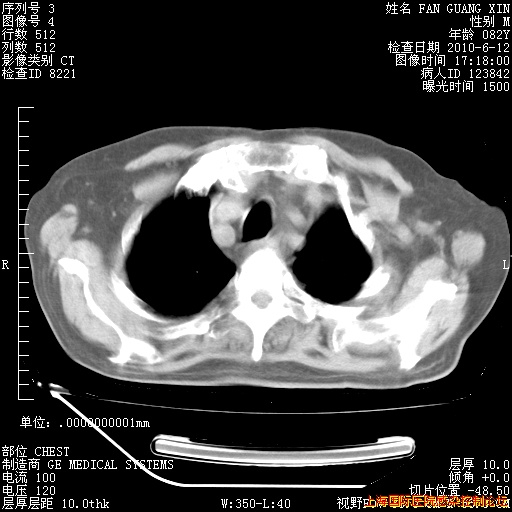

6月12日肺窗

补发6月12日肺部CT肺窗